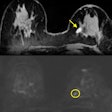

Multiparametric MRI shines for suspected breast cancer

Hyperechogenic breast lesions: Not so benign